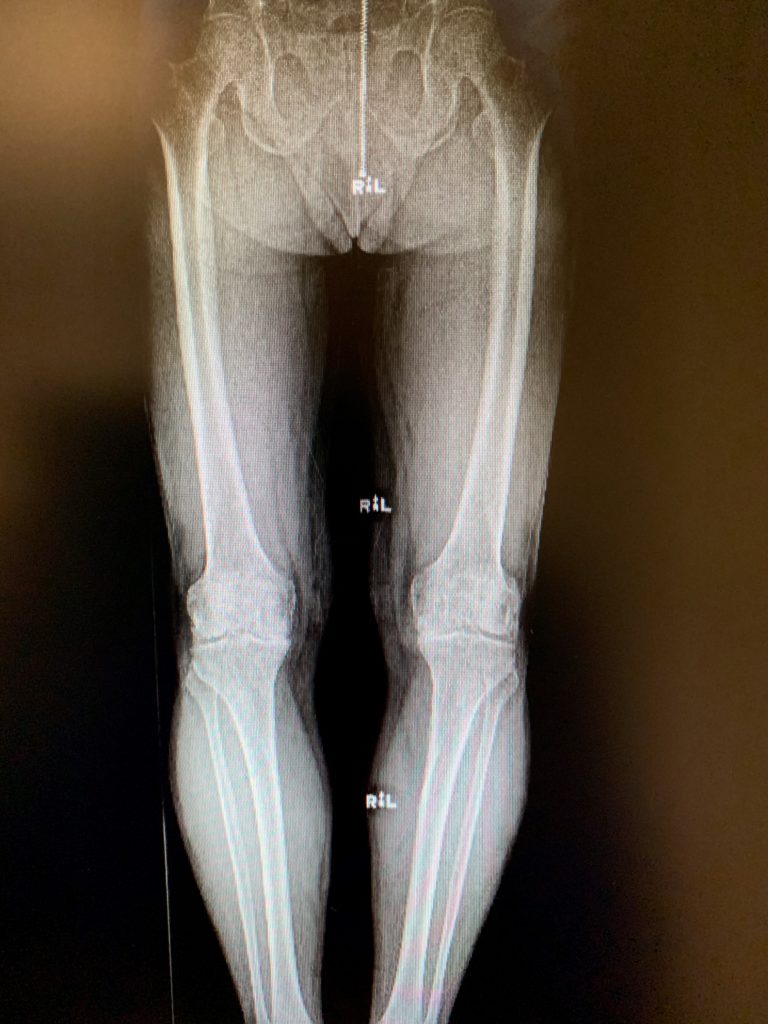

Case Study Bilateral Knee replacement in 54 yr. Old Female Case Study Knee Replacement Imaging revealed severe tricompartmental osteoarthritis of the left knee with joint space reduction and osteophytes. All the risks, benefits and alternatives were. Our case study is the first in the literature to describe a case of a primary total knee replacement performed with a hinged. Considering the lifestyle limiting knee pain, the patient was advised right total knee replacement. In. Case Study Knee Replacement.

Case Study Simultaneous bilateral knee replacement in a 54 year old female Complete Case Study Knee Replacement In this study, we present a case of ochronosis arthropathy treated with tka to contribute to the literature. Considering the lifestyle limiting knee pain, the patient was advised right total knee replacement. This case study is about custom right total knee replacement with prior acl reconstruction from complete orthopedics, with multiple locations around ny. Strength, range of motion and balance. Case Study Knee Replacement.

Case Study Bilateral Customized Total Knee Replacement in a 72yearold female Complete Case Study Knee Replacement In this study, we present a case of ochronosis arthropathy treated with tka to contribute to the literature. Imaging revealed severe tricompartmental osteoarthritis of the left knee with joint space reduction and osteophytes. Our case study is the first in the literature to describe a case of a primary total knee replacement performed with a hinged. Considering the lifestyle limiting. Case Study Knee Replacement.